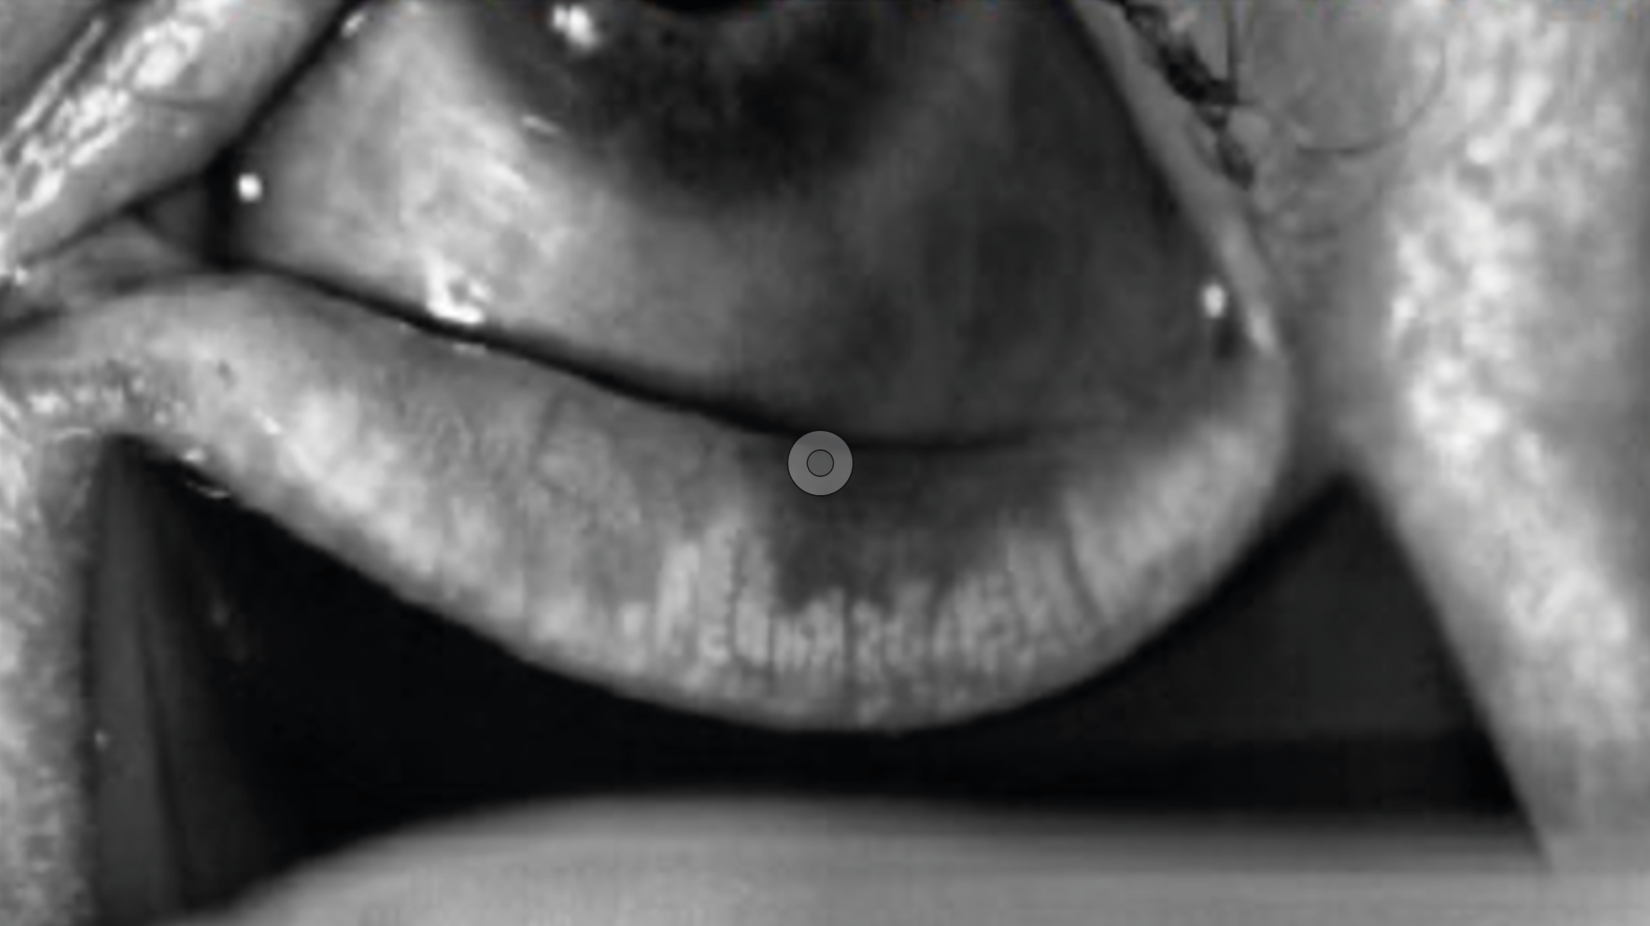

Figure 2. Examen à la lampe à fente avec la LRPG Menicon Rose K2 PG. À gauche : Examen lumière blanche : LRPG en position supérieure, corectopie et atrophie irienne en rapport avec le syndrome ICE. À droite : Examen à la fluorescéine après adaptation ; la lentille est prescrite à l’essai.

Figure 3. Examen à la lampe à fente de l’adaptation en piggy back avec LRPG Menicon Rose K2 PG et LSH Alcon Dailies Total One. À gauche : Examen à la fluorescéine satisfaisant, présence de bulles de pose ; il conviendra de revoir la manipulation pour les éviter. À gauche : Examen en lumière blanche, LRPG décentrée vers le haut.